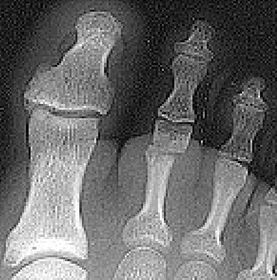

What disease is this? What is shown by A, B and C? | Psoriatic arthritis. A = destructive changes B = Pencil in cup deformity C = IPJ fusion |

What disease is this? | Psoriatic arthritis |

What disease is this? What does the arrow show? | Non-articular psoriatic arthritis Arrow = 'fluffy spur' |